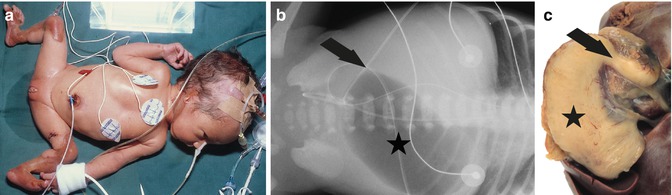

Fig. 37.3

Lethal junctional epidermolysis bullosa with pyloric atresia (EB 033–01) shows cutis aplasia of lower legs and ears (a). X-ray abdomen (b) reveals gastric bubble (asterisk) and airless intestines due to pyloric obstruction (arrow). Preparation of stomach (asterisk) at autopsy shows pyloric atresia (arrow) (c)